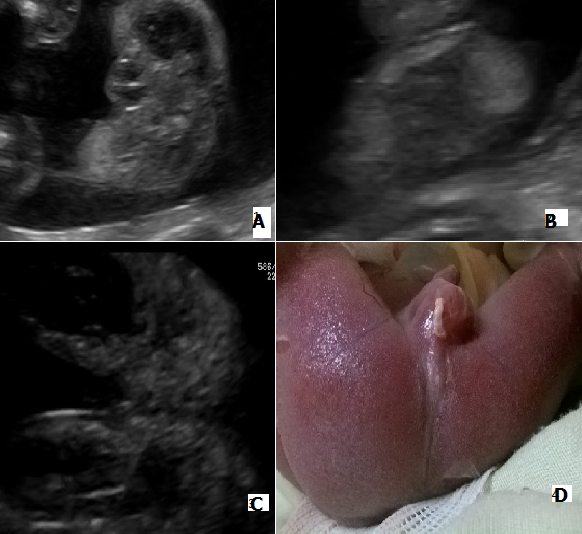

Il s’agit d’une patiente adressée à notre unité de diagnostic anténatal pour suspicion de spina bifida à un terme de 22 semaines d’aménorrhée. Le bilan morphologique trouvait un rachischisis associé à un Chiari II, un rein unique et une malformation anorectale. L’absence de visualisation du complexe sphinctérien anorectal (CSAR) à l’échographie faisait suspecter une malformation anorectale haute (A, B, C). L’examen échographique ne montrait ni anomalies des membres, ni cardiopathies, ni signes en faveurs d’une atrésie de l’œsophage. Un caryotype sur liquide amniotique a été réalisé et le résultat ne montrait pas d’anomalies (46, XY). Une interruption de la grossesse a été demandée par les parents après explication du pronostic fœtal montrant une absence d’anus (D). L’examen fœtopathologique permet de confirmer la nature haute ou basse de la malformation anorectale par l’absence de CSAR et les anomalies associées.